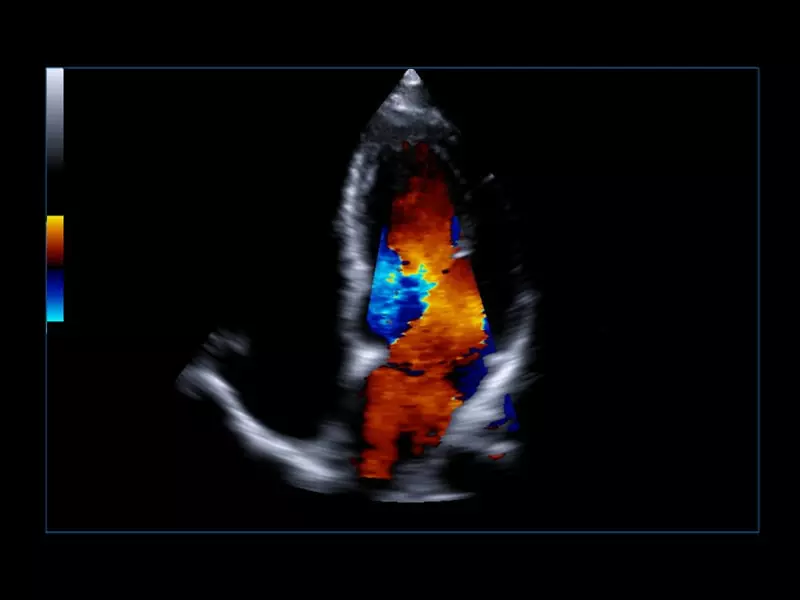

Q7 - Cardio CFM

Q7 - Cardio CFM